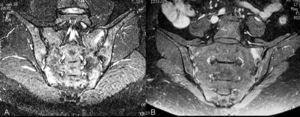

Doce pacientes mostraron una disminución de la puntuación ASspiMRIa, y una menor afectación en ASI y coxofemorales en la RM realizada tras el tratamiento (fig. 4). En el paciente restante, con puntuaciones de 0 en columna, sacroilíacas y caderas, no se modificaron las mismas tras el tratamiento.

Fig. 4.--Disminución de la afectación inflamatoria en articulaciones sacroiliacas tras el tratamiento. A: basal. B: transcurridos seis meses.